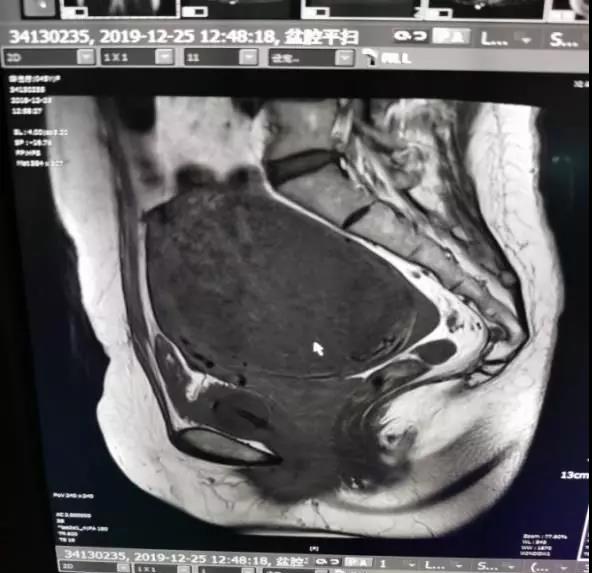

初見侯阿姨的時候,醫(yī)護人員都以為侯阿姨患的是宮體肌瘤(子宮肌瘤從生長部位上分為宮體肌瘤和宮頸肌瘤)。經(jīng)過詳細的查體、婦科檢查和盆腔B超,侯阿姨被確診為宮頸肌瘤,而且瘤體巨大,約15?11cm?10cm。宮頸肌瘤本就不多見,像侯阿姨這種瘤體大且宮底已經(jīng)平臍,更是罕見。

通過磁共振造影確定腫瘤位置后,醫(yī)護人員發(fā)現(xiàn),侯阿姨的肌瘤瘤體大,生長位置低,毗鄰輸尿管、子宮動脈等重要器官,瘤體血供豐富,這無疑預(yù)示著這次手術(shù)的難度與風險。